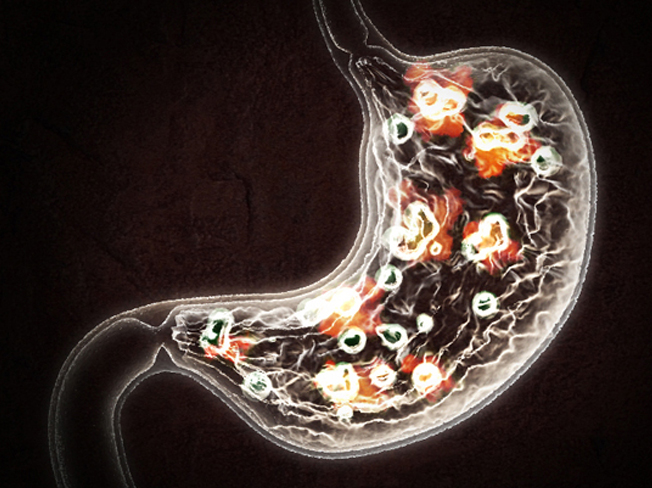

홍보, 학회 발표, 수술 교육, 의학 제품 소개와 관련한 영상을 3D로 제작하여 제공해드립니다.

제작범위 : 신체 전신, 뼈대, 장기, 혈관 등 사람, 동물의 모든 표현이 가능하며, 수술과 관련한 도구 제작도 가능합니다.